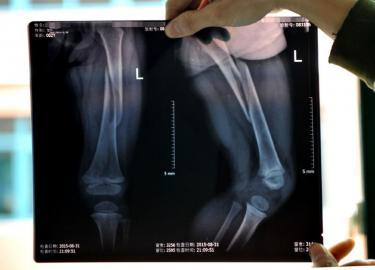

9月4日,摔断腿的佳佳在医院接受治疗。

X光片显示佳佳左腿骨折。 9月4日,成都新都龙桥镇一家医院里,两岁半的女童佳佳(化名)躺在病床上,她的左腿被硬邦邦的几块木板固定着。尽管医生给她打了缓解疼痛的药物,她还是疼痛得不停冒汗。 4天前,妈妈彭女士带着佳佳到龙桥镇瑞云社区的广场玩耍。广场上有一个移动的充气蹦蹦床,彭女士花了5元钱让佳佳在上面玩耍。玩了一阵后,蹦蹦跳跳的佳佳突然趴在气垫上没有再起来。彭女士带女儿到医院检查,医生诊断佳佳的左大腿的股骨干断了。该游乐设施的经营者陪同把孩子送往医院后,就再也没有出现过。目前,新都斑竹园工商所已介入调查。 女童突然趴着不起来 医院诊断其左腿骨折 4日下午,在新都一家医院里,记者见到了躺在病床上的佳佳。她的左腿被几块木板固定着,缠着厚厚的绷带,医生刚给她打过止痛针,她情绪安稳了些。天气并不热,她的额头和背上不停冒汗。彭女士握着女儿的小手,一边轻轻地给她扇扇子,眼里满是懊恼和无奈。“如果那天我不带她去,她就不会这么造孽。” 彭女士说,8月31日下午,她带着佳佳到广场玩耍。广场上有一个移动的充气蹦蹦床。因为看着上面有十几个小孩在玩耍,佳佳也嚷着要去玩。彭女士说,只要给5元钱,就可以在上面玩一下午。佳佳从下午4点左右开始玩,一直玩到晚上8点,佳佳和其他小伙伴玩得非常开心,又蹦又跳的。 “我怎么也没想到会出事!”彭女士说,当时她就在一旁看着女儿,距离只有1米左右。“她跳着跳着,突然趴在地上不动了。”彭女士以为孩子玩累了,准备把孩子抱回去,却怎么叫她都不起来。“遭了,断了!”彭女士走过去,把孩子抱起来,这时她的手摸到孩子的左腿,发现里面的骨头已经松动了。彭女士把情况告诉了该游乐设施的老板,双方一起把孩子送到了附近一家医院检查,拍片显示:佳佳的左腿股骨干螺旋形骨折。也就是说,佳佳左腿大腿的骨头已经断了。 孩子须及时转院治疗 否则左腿将终身残疾 彭女士说,蹦蹦床的老板把孩子送到医院后,就悄悄离开了医院,只留下了一个电话,之后就一直找不到人。 彭女士一家是宜宾人,因为丈夫林先生在家具厂打工,一家人就在附近租了房子。平时林先生打工每月工资不到3000元,彭女士专门负责看管孩子。彭女士说,医生告诉她,孩子必须及时转到更好的医院治疗,否则耽误了伤情,会落下左腿终身残疾的病根。然而,找不到游乐设施的老板,对于彭女士一家来说,转到更好的医院似乎成为了奢望。“医生说治疗需要几万元,可是我们没有任何积蓄!”说着说着,佳佳的爸爸林先生眼睛都红了。 4日,记者来到了事发地点,包括当时的目击者陈女士在内的当地多位居民,向记者证实了佳佳在充气蹦蹦床上摔断腿一事。目击者陈女士也带着孩子在现场玩耍,出事后她很快带着孩子离开了。陈女士说,当时玩耍的有20多个孩子,小的才刚会走路,大的已经差不多10岁。 多位居民告诉记者,基本每天下午3点过后,就有人运来蹦蹦床。冲上气,然后把它放在广场的中央供小孩玩耍。只要交5元钱,就可以在上面玩耍一下午。 4日下午,记者在现场等待了一下午,都没见到移动充气蹦蹦床出现,也未见到老板。附近多位居民说,出事后老板再也没出现过。记者拨打老板当时留下的电话,说明采访来意后,对方挂掉了电话。随后,记者多次拨打,对方仍不原接受采访。记者又发去多条短信,截至发稿前,对方没有回复。 4日下午,新都斑竹园工商所相关负责人也来到了现场,他们也无法找到移动充气蹦蹦床的老板。对于充气蹦蹦床质量是否合格、经营者是否有相关经营资质等问题,目前工商部门已展开调查。记者李秀江 摄影张磊 |